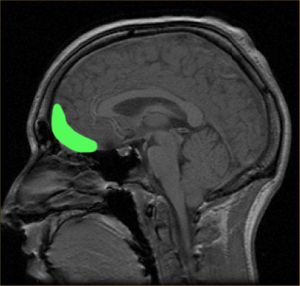

الأسباب

في الأساس يعتبر العلماء أن عامل الوراثة هو الأساس، حيث تنتقل الصبغات الوراثية بالجينات من الاباء إلى الأبناء، كما يوجد نظريات تحيل الحالة إلى خلل في الهرمونات والجهاز العصبي.